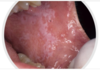

Reticular lichen planus

Here it is a plaque-like presentation of lichen planus

This is not a classic presentation.

Would still get a biopsy to confirm.

Bilateral asymptomatic white lesions of the buccal mucosa

Wickman striae lace-like appearance.

Plaque-like areas.

Normally not painful.

Can be in different surfaces like the alveolar mucosa and then onto the vestibular appearance involved.